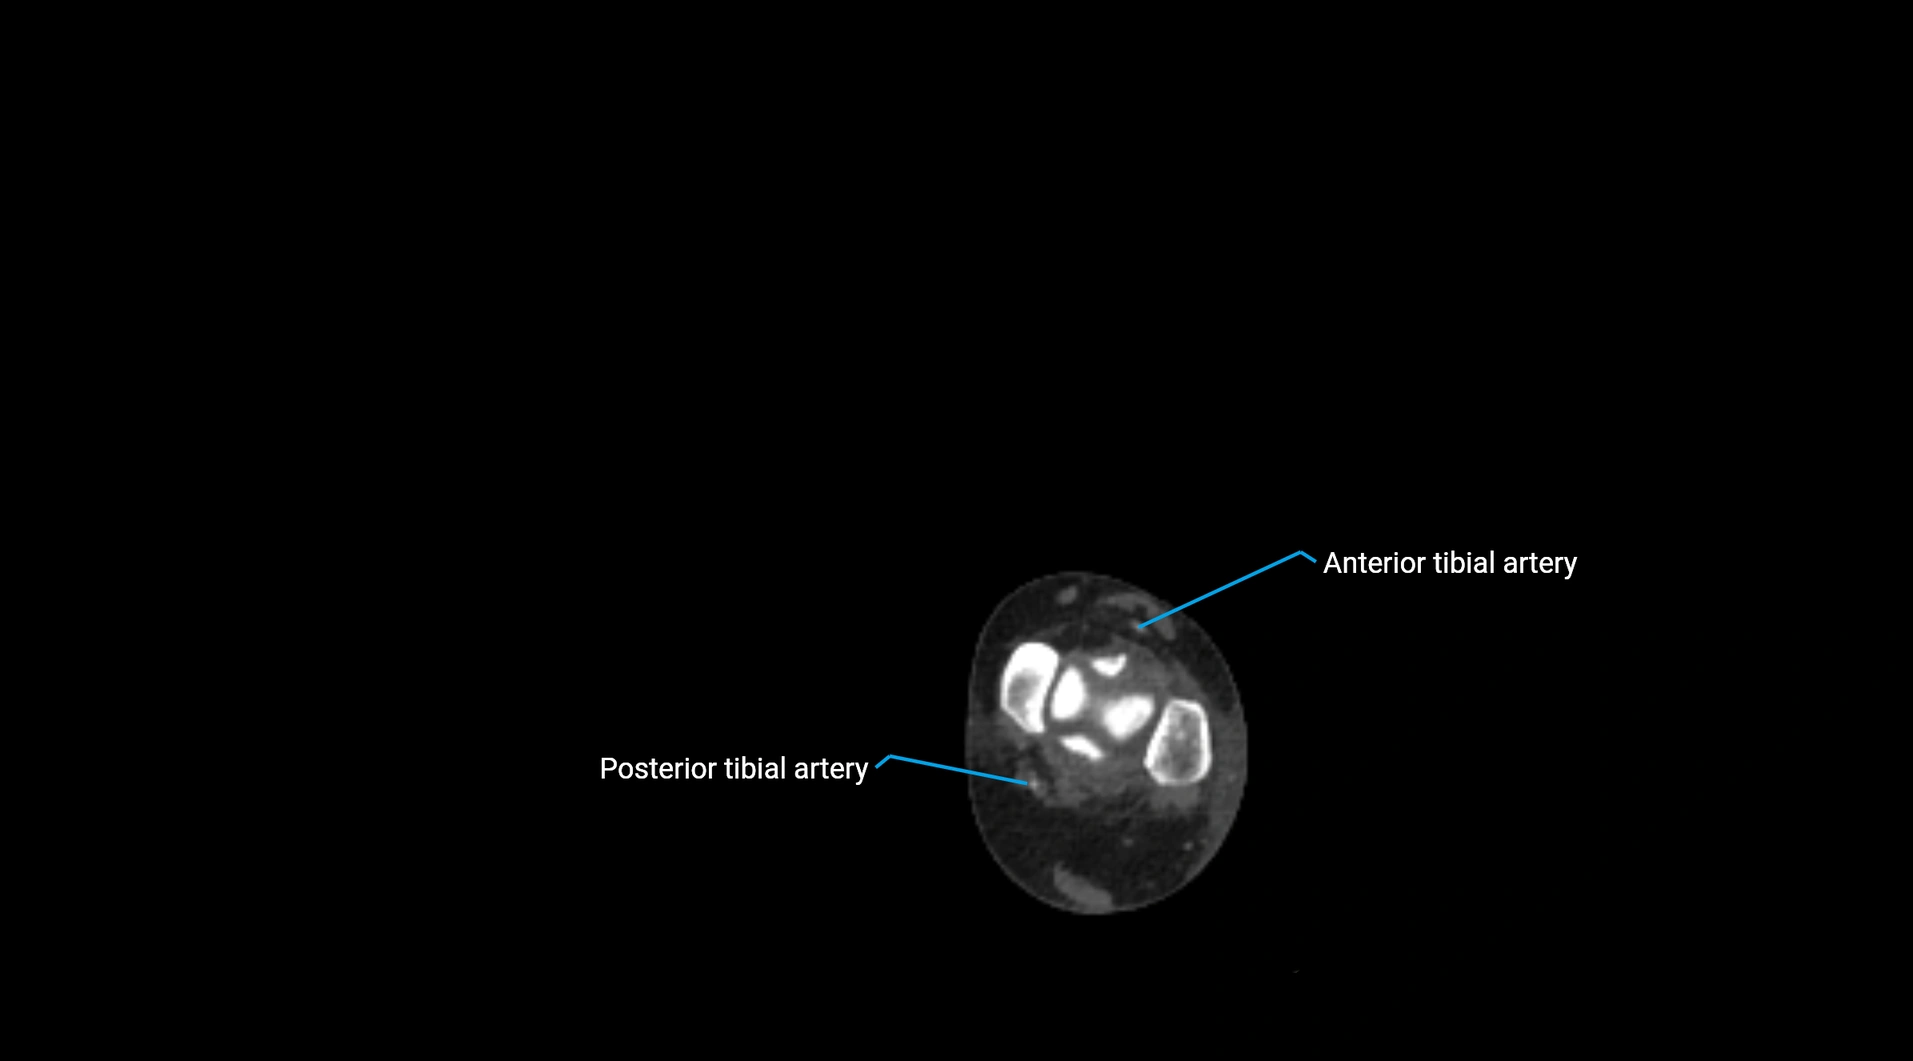

CT images

image

CT Appearance

Non-contrast CT:

• Appears as a tubular soft tissue structure anterior to vertebral bodies

• Calcified atherosclerotic plaques appear as hyperdense foci along the wall

• Useful for screening abdominal aortic aneurysm (AAA) size and mural calcification

Contrast-enhanced CT (CTA):

• Gold standard for abdominal aortic imaging

• Provides excellent detail of lumen, wall, aneurysm, thrombus, and branch vessels

• Multiplanar and 3D reconstructions help in aneurysm measurement, stent graft planning, and dissection evaluation

• Detects acute rupture, traumatic injury, or occlusion with high sensitivity